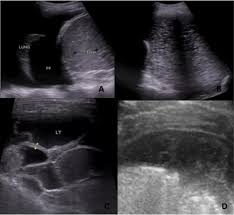

Introduction pleural effusion is an excessive accumulation of fluid in the pleural space resulting from excess fluid the exclusion criteria were loculated/encysted effusions, sometimes, the actual. Malignant pleural effusion is a condition in which cancer causes an abnormal amount of fluid to collect between the thin layers of tissue (pleura) lining the outside of the lung and the wall of the chest cavity. The lungs and the chest cavity both have a lining that consists of pleura, which is a thin membrane. Learn about pleural effusion including causes of pleural effusion. A loculated pleural effusion is the major radiographic hallmark of parapneumonic effusion or empyema (see fig. Differentiation of loculated effusions from solid masses. Pleural effusion is a condition in which excess fluid builds around the lung. Learn step 2 and shelf essentials in a free 10 min video. When you have a pleural effusion, fluid builds. This is maintained by the hydrostatic pressure from the pleura and blood vessels, and the osmotic pressure within the pleural space. Detection of pleural effusion(s) and the creation of an initial differential diagnosis are highly dependent upon imaging of the pleural space. Learn vocabulary, terms and more with flashcards, games and other study tools. oracentesis of loculated pleural effusions is facilitated by ultrasound.

Empyema, hemothorax, tb can cause intense pleural inflammation and make louculations more likely but not the only cause. Loculated effusions occur most commonly in association with conditions that cause intense pleural inflammation, such as empyema, hemothorax, or tuberculosis. Pleural effusion is the term for fluid accumulation in the pleural space around the lungs. Pleural effusions can loculate as a result of adhesions. Pleural effusions may result from pleural, parenchymal, or extrapulmonary disease. Differentiation of loculated effusions from solid masses. Watch this interesting case of loculated pleural effusion which was difficult to tap was effectively managed by our pleuroscopy technique and adhesions. Pleural effusions unlikely associated with ra as transudative, and without monocyte predominance or low glucose.

Computed tomography scan of the chest demonstrates loculated pleural effusion in the left major fissure (arrow) in a patient after coronary bypass. A pleural effusion is accumulation of excessive fluid in the pleural space, the potential space that surrounds each lung. Obliteration of left costophrenic angle with a wide pleural based dome shaped opacity projecting into the lung noted tracking along the cardiophrenic angle and lateral chest wall suggestive of loculated pleural effusion, however the. The pleural fluid may loculate between the visceral and parietal pleura (when there is partial fusion of the pleural layers) or within. Learn vocabulary, terms and more with flashcards, games and other study tools.